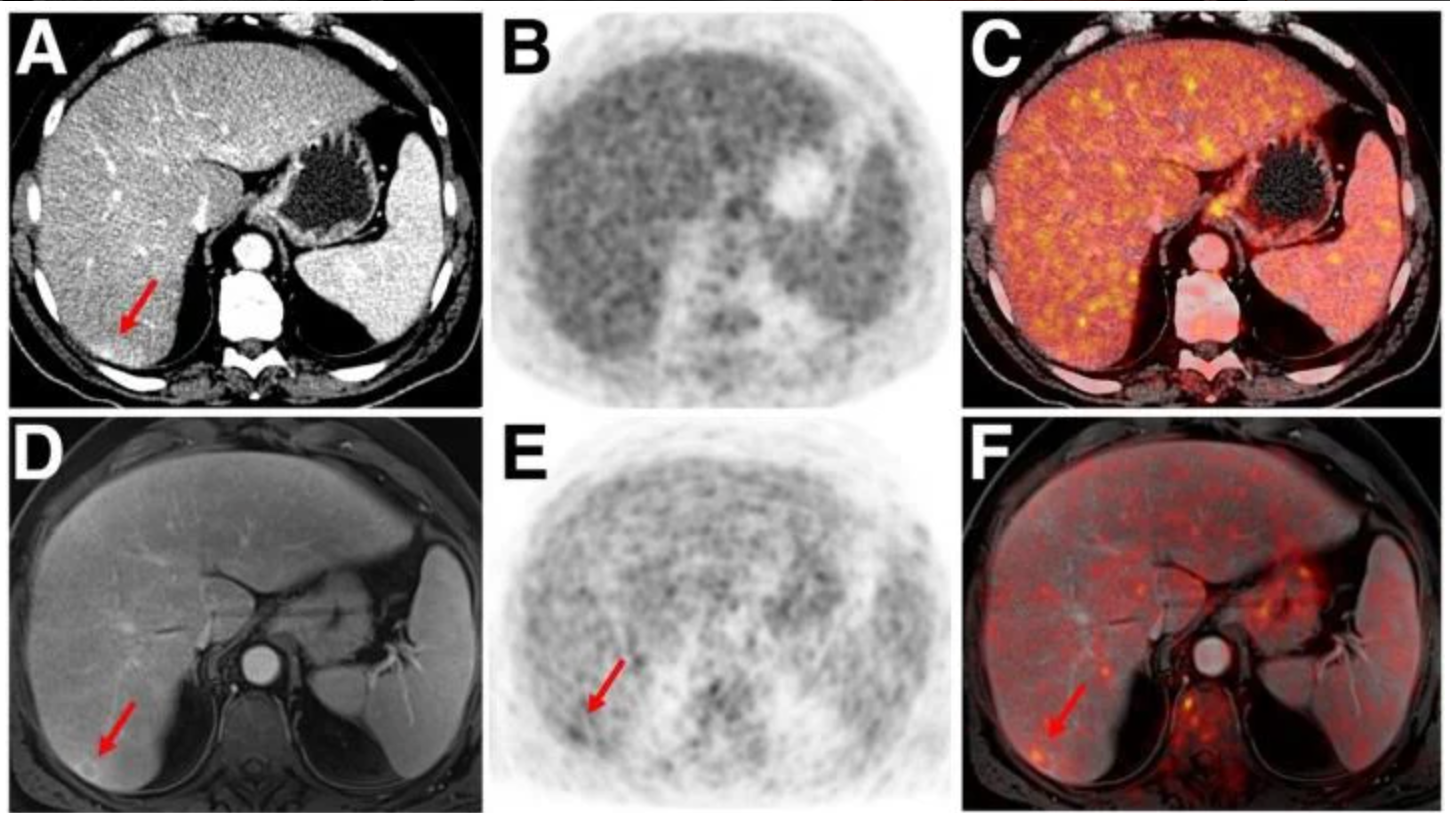

68Ga-pentixafor can clearly distinguish between healthy and malignant tissue on both CT and MRI scans.